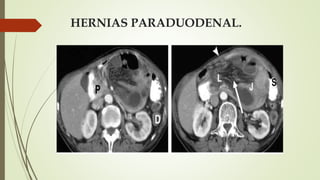

HERNIAS PARADUODENAL.

 Las fosas paraduodenales se originan como anomalías peritoneales

congénitas debido al fracaso de la fusión mesentérica con el peritoneo

parietal y una rotación anormal asociada durante el encarcelamiento del

intestino delgado bajo el colon en desarrollo

HERNIAS PARADUODENAL